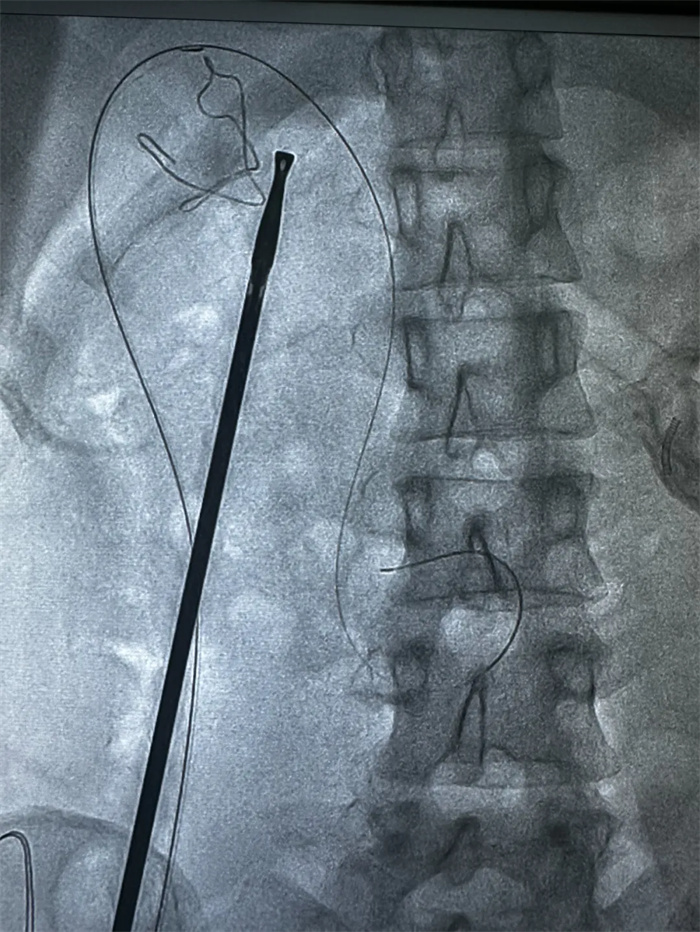

手術(shù)中,榮譽院長楊闖、主治醫(yī)師曹君貴首先進行了LC術(shù),術(shù)中經(jīng)膽囊管插管后,由曹君貴主治醫(yī)師再行ERCP+EST取石+ENBD術(shù),順利解決膽總管結(jié)石。